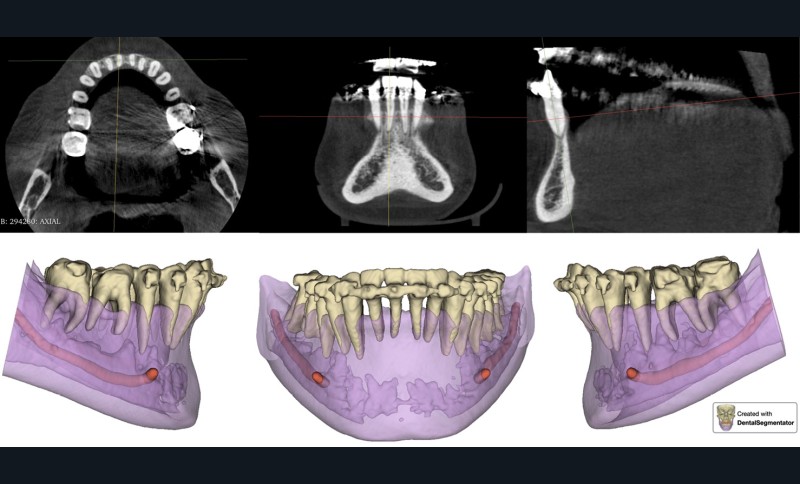

L’examen radiographique (fig. 3-5) nous indique une Classe I squelettique de Ballard (ANB 0°) sur un schéma facial à tendance hyperdivergent (FMA 28°). L’analyse céphalométrique confirme la vestibulo-version incisive (I/SN 111° ; IMPA 94°). La lyse osseuse est généralisée.

En raison de l’ancrage dentaire postérieur mandibulaire très limité, il est décidé d’utiliser des ancrages osseux pour l’ingression du bloc incisivo-canin mandibulaire, afin de niveler l’arcade et de recréer le surplomb nécessaire à la fermeture des diastèmes maxillaires. Deux minivis d’ancrage sont positionnées entre les dents 32/33 et 42/43, après réalisation d’un examen CBCT localisé sur l’arcade mandibulaire (fig. 7 et 8). Ces minivis antérieures ont été rapidement déposées, en raison de leur mobilité et de la gêne importante de la patiente liée au positionnement très apical du fait de l’alvéolyse.